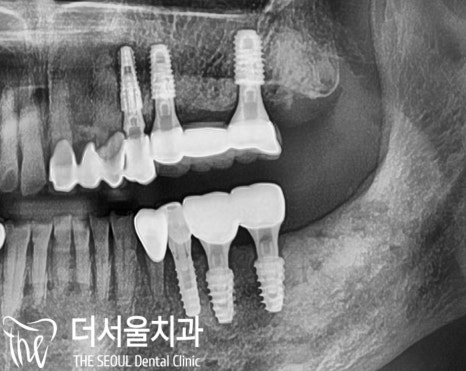

이후 구강 환경 고려 후

인공치근인 픽스처를 심고

임시치아까지 올려 드렸습니다.

윗니 전치부 치은에서도

특이 소견이 보여 체크한 결과

구강환경에 맞게 보철을

재 제작해 드림으로 치주 질환에

부담을 덜어드렸습니다.

오늘 소개해 드린 환자의

연세는 80대셨는데

이전과 달리 음식을 먹는데

너무 편하시다며 매우 기뻐하셨습니다.